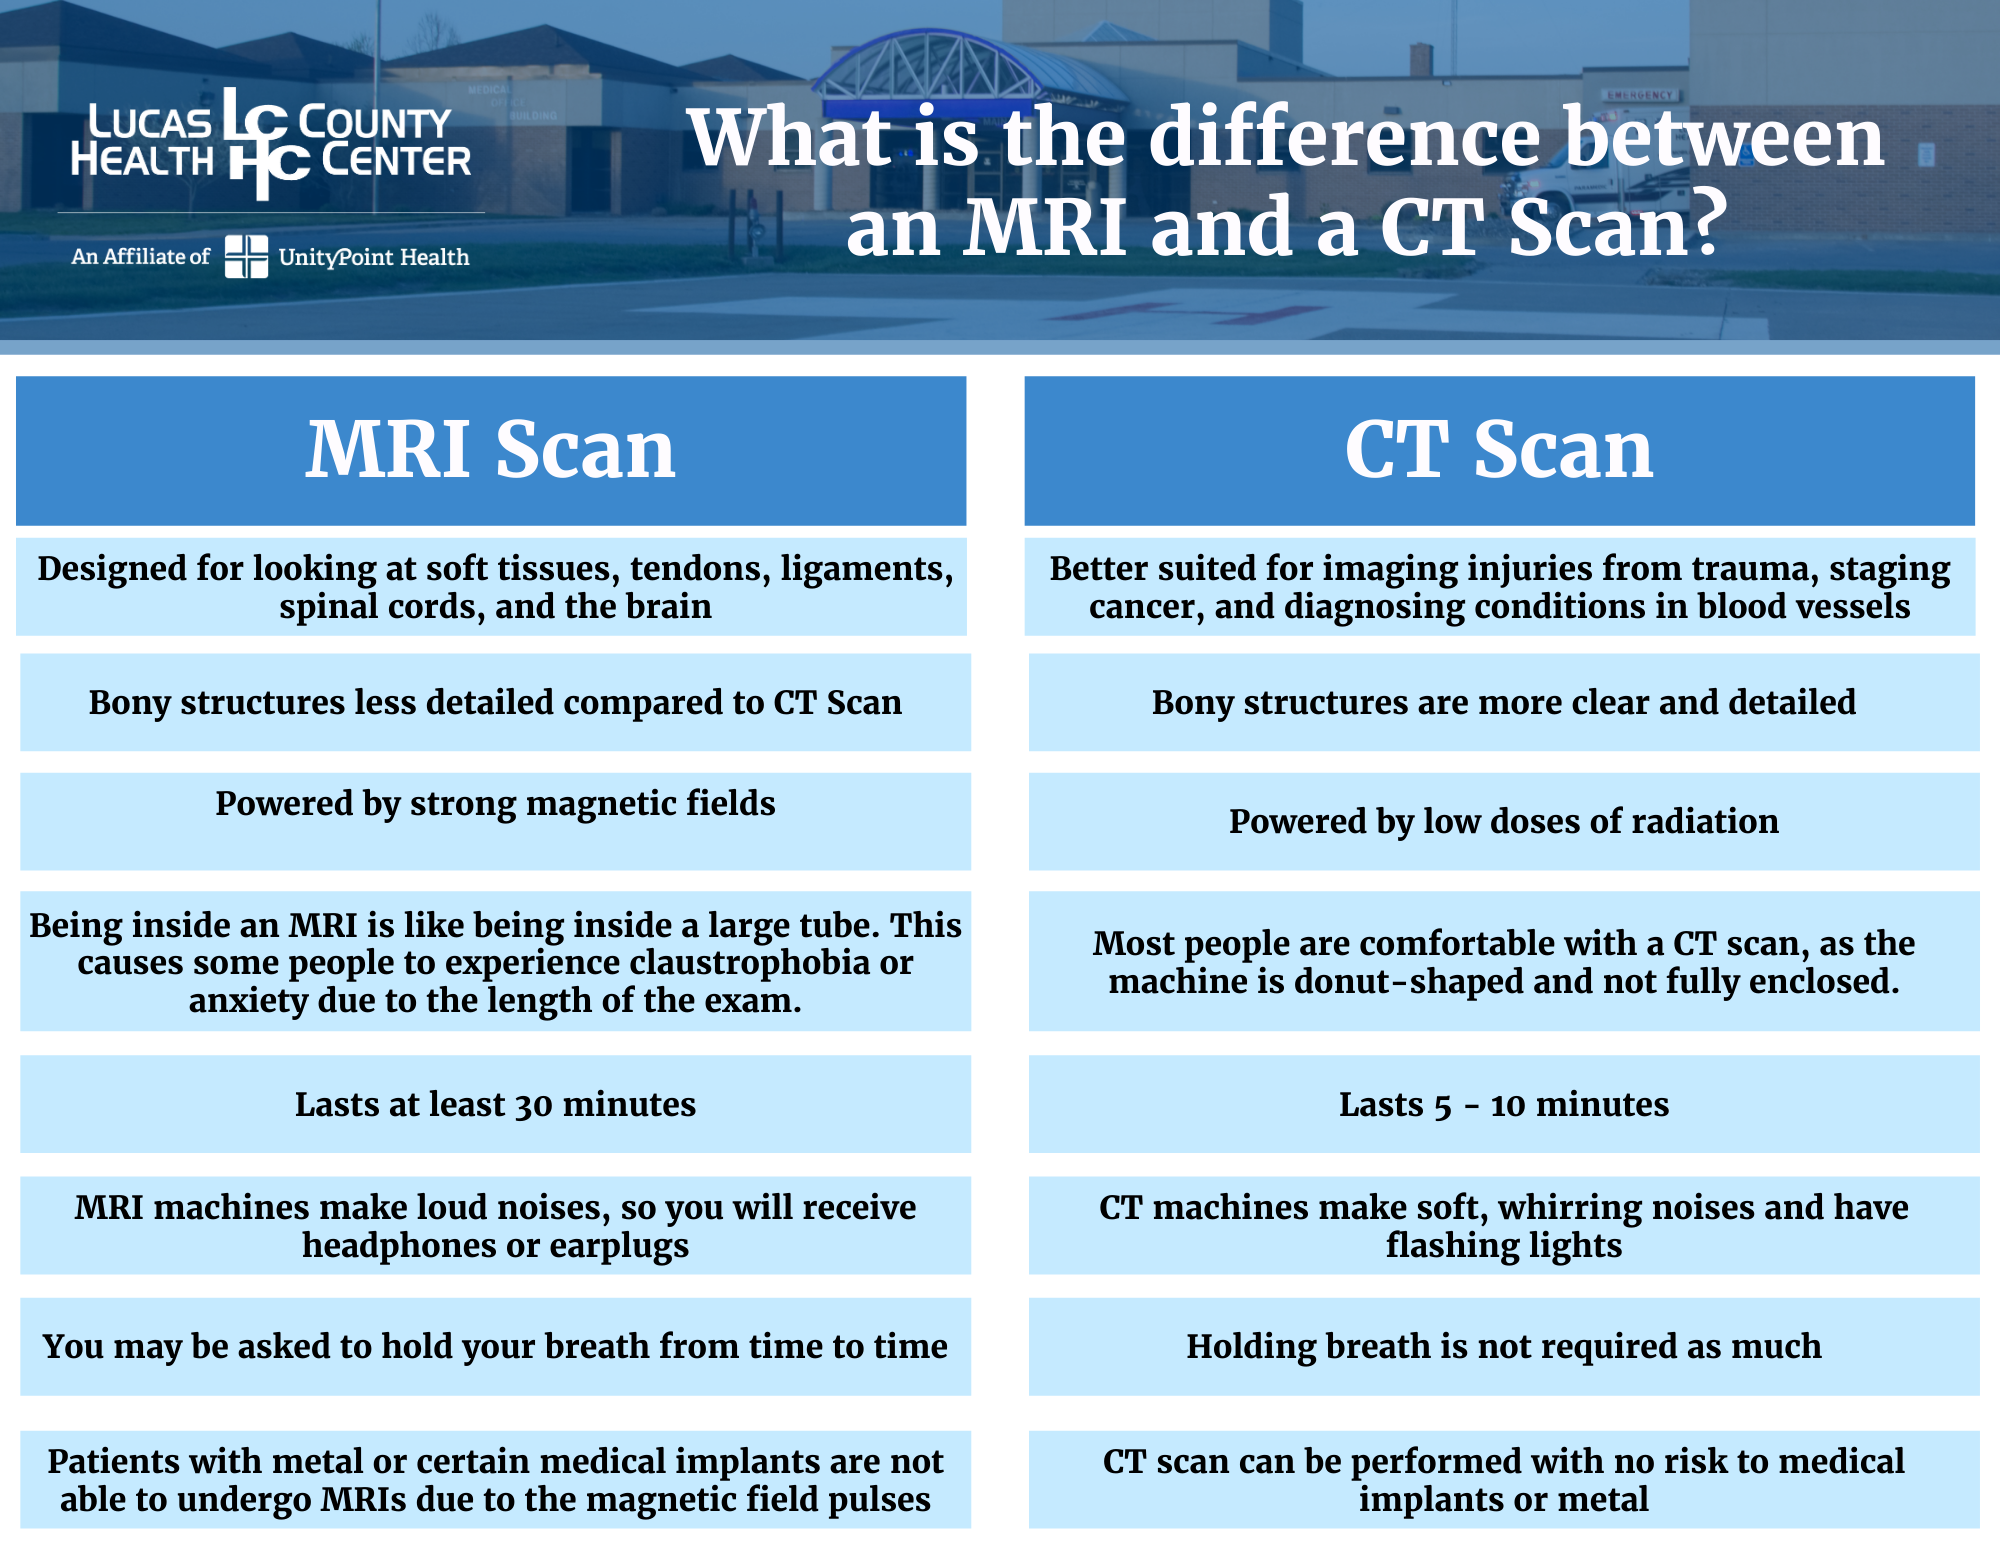

MRI Vs CT Scan Understanding Medical Terms 7ESL

MRI Vs CT Scan Difference

MRI Vs CT Scan Difference